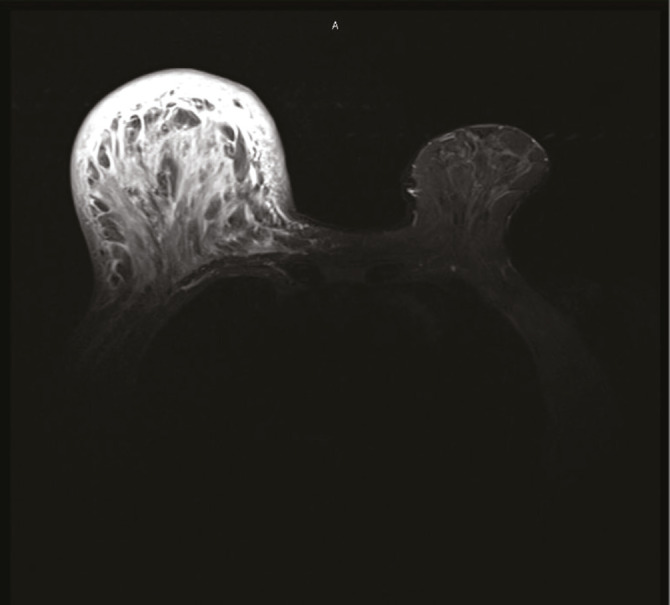

Breast lymphedema is a common but underdiagnosed condition that affects the quality of life of patients. It may be caused by any pathology that disrupts lymphatic drainage in the breast. We present the case of a woman with axillary lymph node tuberculous infection with breast edema, clinically and radiographically indistinguishable from tuberculous mastitis. After six months of comprehensive antituberculosis pharmacological treatment, the persistence of breast edema required repeating diagnostic tests searching for malignancy, all of which were negative. Rehabilitation treatment with complex physical therapy improved the patient's clinical and symptomatic condition. Clinical suspicion of secondary lymphedema is crucial to avoid unnecessary diagnostic procedures and ensure adequate and timely treatment.

Abstract Image